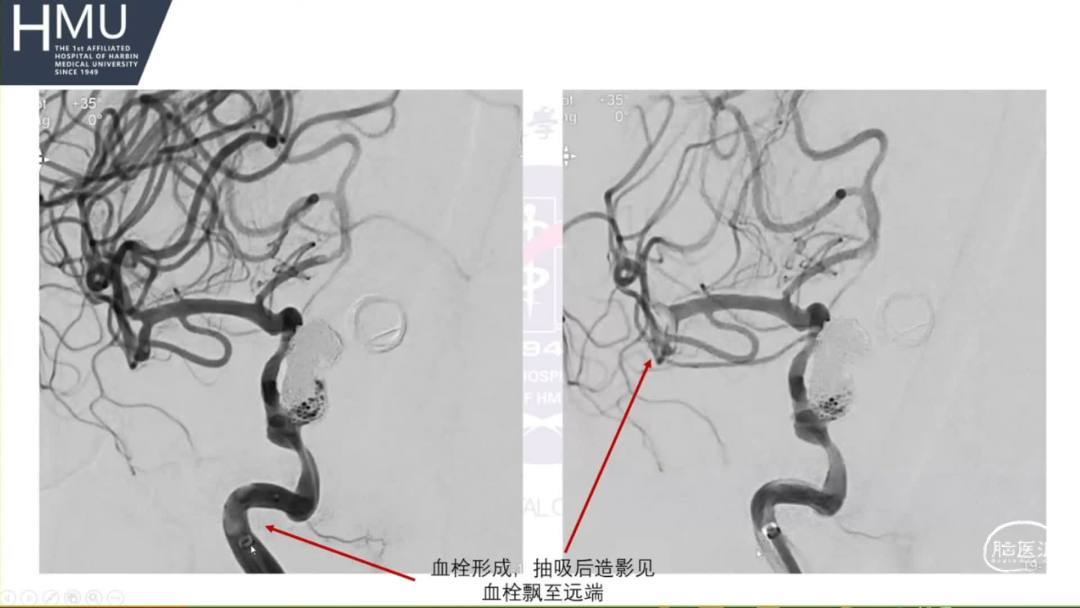

21:00覆膜支架置入术

海绵窦段动脉瘤如何导致蛛网膜下腔出血?